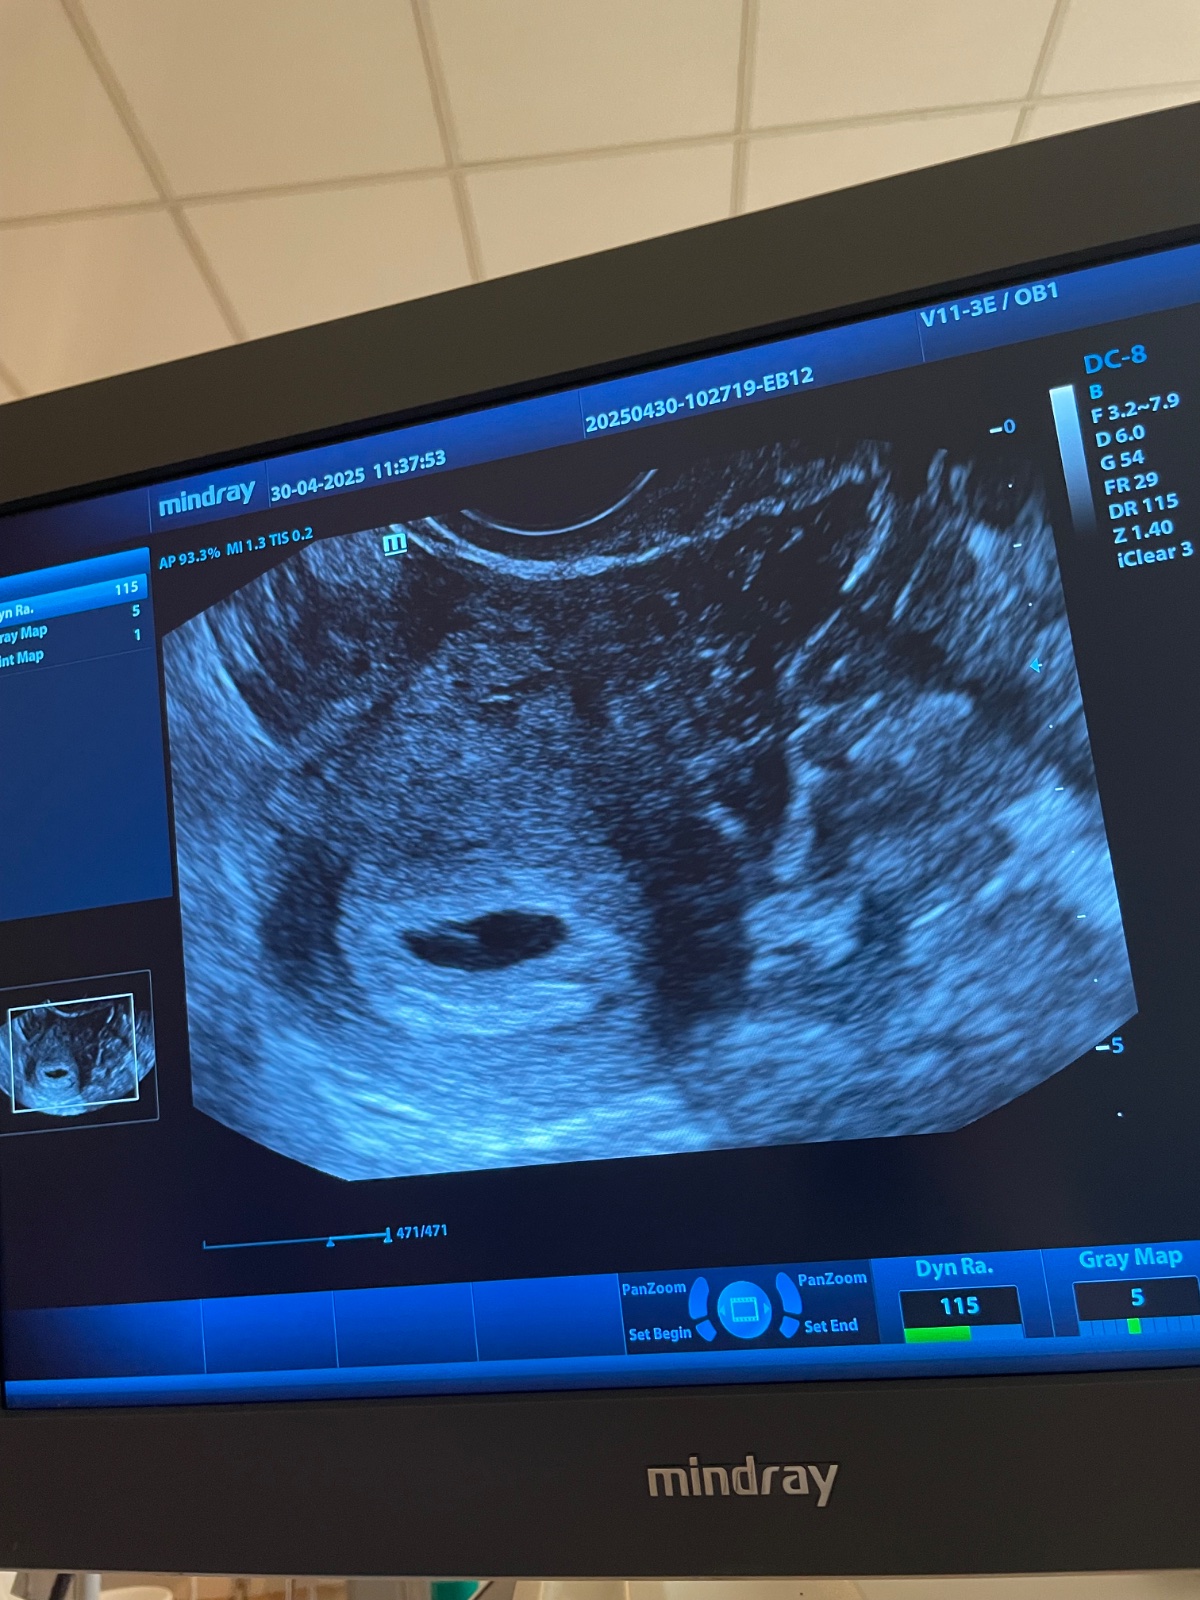

Žĺtkový vak bez plodu

Ahojte. Som 5+4 bola som na kontrole prvý krát

Bol vidieť gestacny vak a zltkovy. Ale nebolo vidieť plod.

Je to Dovre znamenie? 🙏